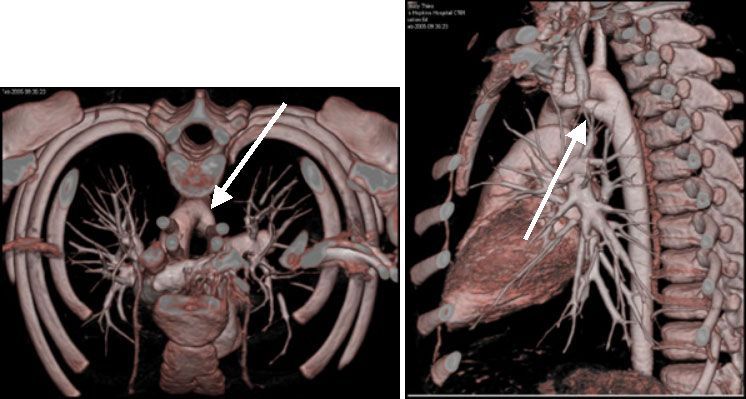

Следующее показание для обследования брюшной аорты и ее ветвей - это злокачественная артериальная гипертензия для выявления стеноза почечных артерий [2,3] (рис № 12).

![]() |

| Рис.12. МСКТ у пациента с вазоренальной артериальной гипертензией. Стеноз правой почечной артерии (стрелка). |

Клиническая картина стенозирующего поражения ветвей аорты также требует уточнения, таким пациентам возможно проведение инвазивной аортоангиографии (ААГ) или более удобной МСКТ (рис №.13,14).

| Рис.13-14. МСКТ 3-D реконструкция брюшной аорты и периферических артерий. Справа: стеноз верхней мезентериальной артерии (стрелка). Слева: окклюзия правой подвздошной артерии (стрелка). |